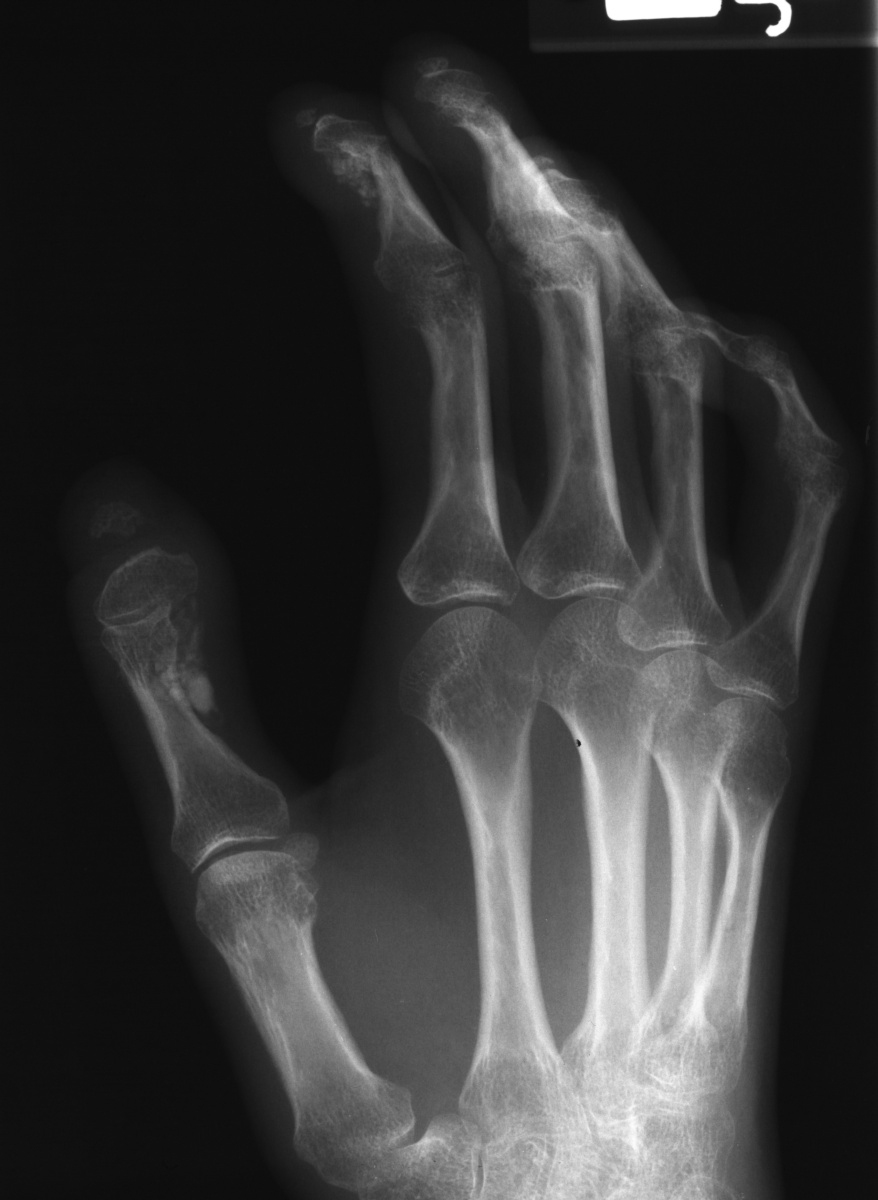

Clinical Example: Scleroderma, Calcinosis and Acroosteolysis

Scleroderma is a polymorphic condition , variably associated with a variety of conditions including joint stiffness, subcutaneous calcification and acroosteolysis. This patient with scleroderma demonstrates all of these conditions. This is most commonly associated with the finding of anticentromere antibodies.